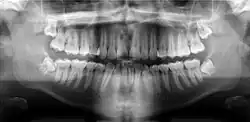

Panoramic(figure 1) and apical(figure 2) radiographs are commonly utilised in routine examinations to aid in the initial detection of BBC.[15] BBC is characterised by a well-defined radiolucent lesion on the buccal aspect of the tooth extending from furcation to the root apices.[19][20] With the presence of periosteal reaction on the buccal aspect of the tooth.[21][22] Tilting of the affected molars, with the apices of the roots tilted lingually and cusp tip buccally.[21][22] Unlike a periapical cyst, the periodontal ligament space and lamina dura remain intact and continuous, suggesting that the lesion is not directly associated with the root apices.[15][21][22]

Panoramic and periapical X-rays are usually performed first to identify the radiolucency on the buccal aspect of the tooth of interest, without involving the apex of the tooth.[13] The roots of the impacted tooth are usually bound by a well-defined radiolucent lesion.[13]